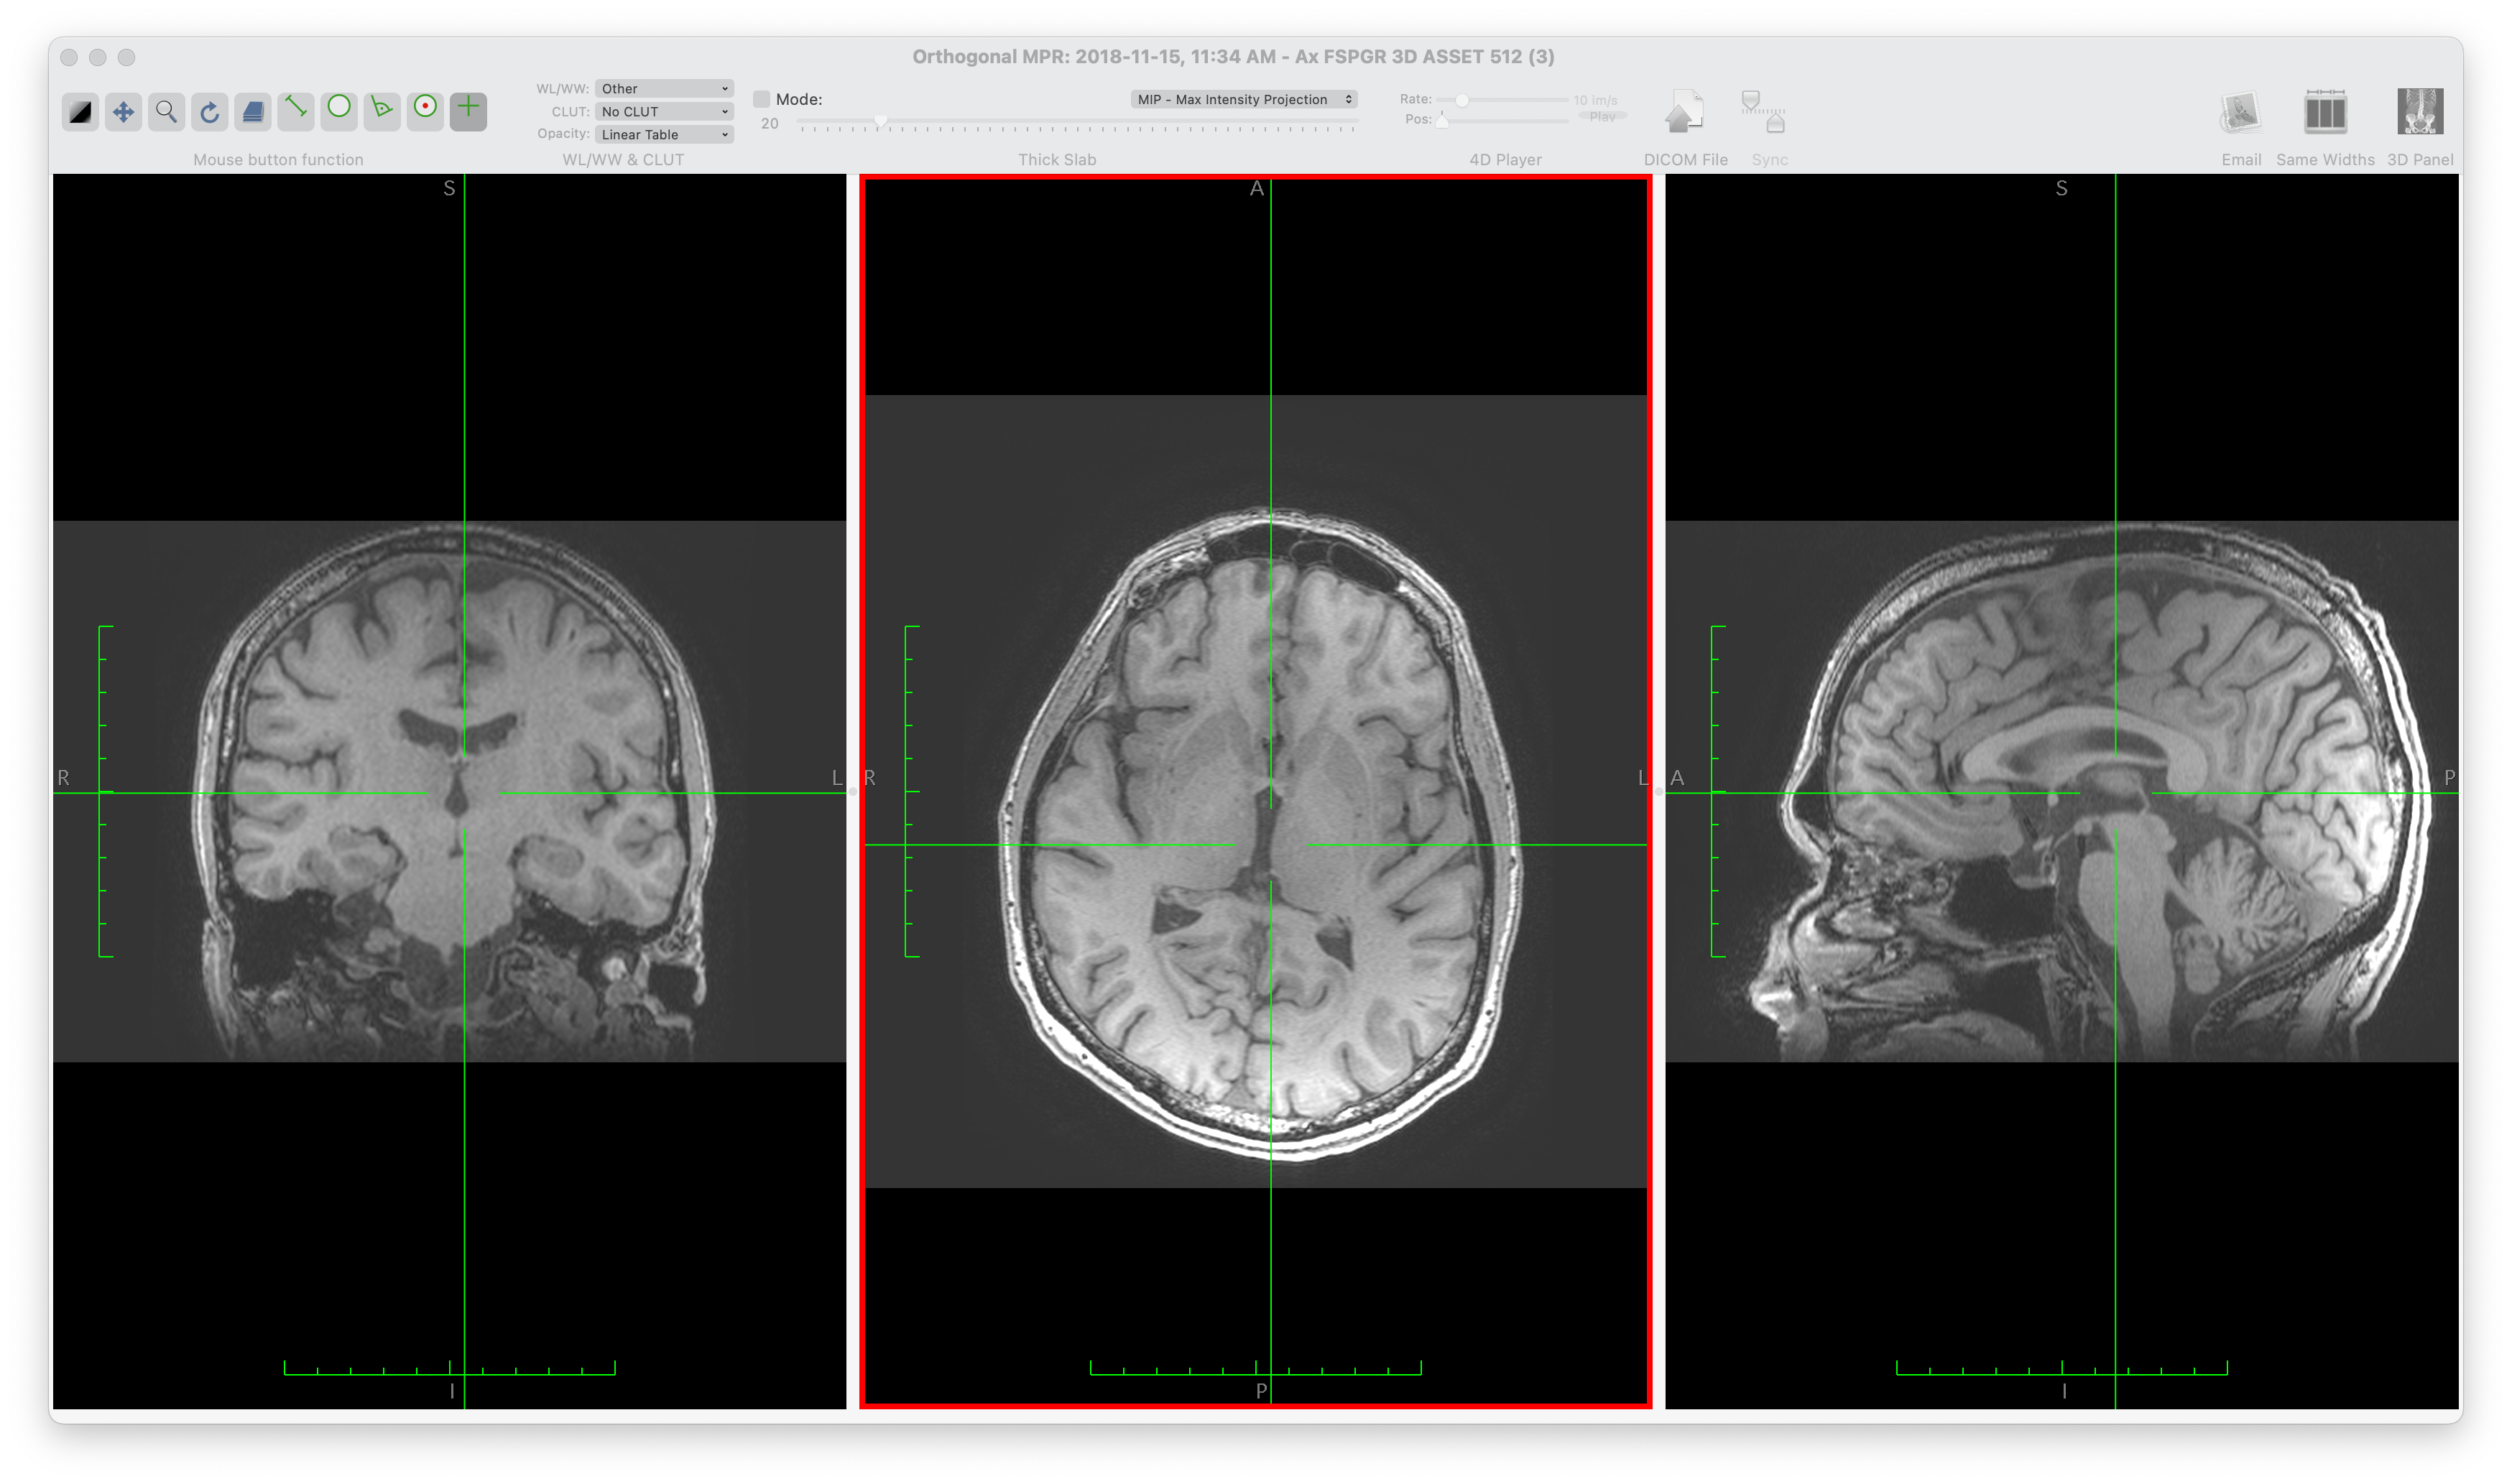

We aim to study the state of software development practice for Medical Imaging (MI) software. MI tools use images of the interior of the body (from sources such as Magnetic Resonance Imaging (MRI), Computed Tomography (CT), Positron Emission Tomography (PET) and Ultrasound) to provide information for diagnostic, analytic, and medical applications (Administration, 2021; Wikipedia contributors, 2021d; Zhang et al., 2008). Figure 1, which shows an image of the brain, highlights the importance and value of MI. Through MI medical practitioners and researchers can noninvasively gain insights into the human body, including information on injuries and illnesses. Given the importance of MI software and the high number of competing software projects, we wish to understand the merits and drawbacks of the current development processes, tools, and methodologies. We aim to assess through a software engineering lens the quality of the existing software with the hope of highlighting standout examples, understanding current pain points and providing guidelines and recommendations for future development.

Figure 1: Example brain image showing a multi-planar reformat using Horos (free open-source medical imaging/DICOM viewer for OSX, based on OsiriX)